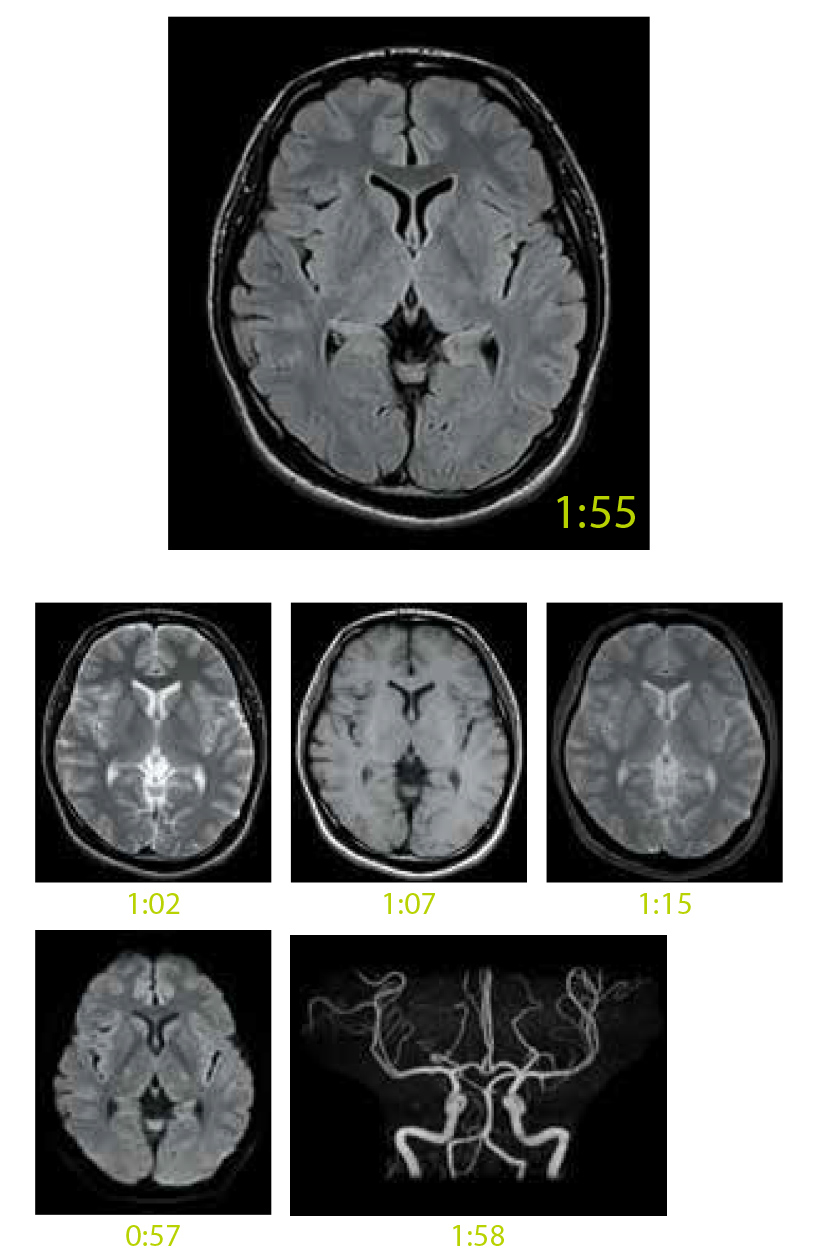

Modern Yüksek Hızlı Görüntüleme Teknolojisi

IP-RAPID, iteratif işleme kullanılan yüksek hızlı görüntülemedir ve IP-RAPID uygulanmayan geleneksel görüntüleme yöntemleriyle benzer görüntü kalitesini korurken tarama sürelerini %60’a kadar azaltır.